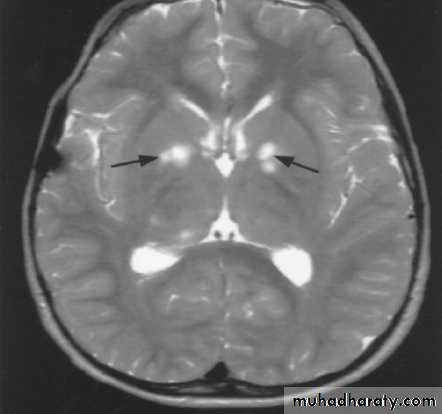

Neurological:learning disabilities, attention deficit disorders, behavioral and psychosocial problems, and abnormalities of speech.

Seizures, hydrocephalus, macrocephaly & vascular abnormalities may lead to TIA & hemiparesis.

Neuroimaging study